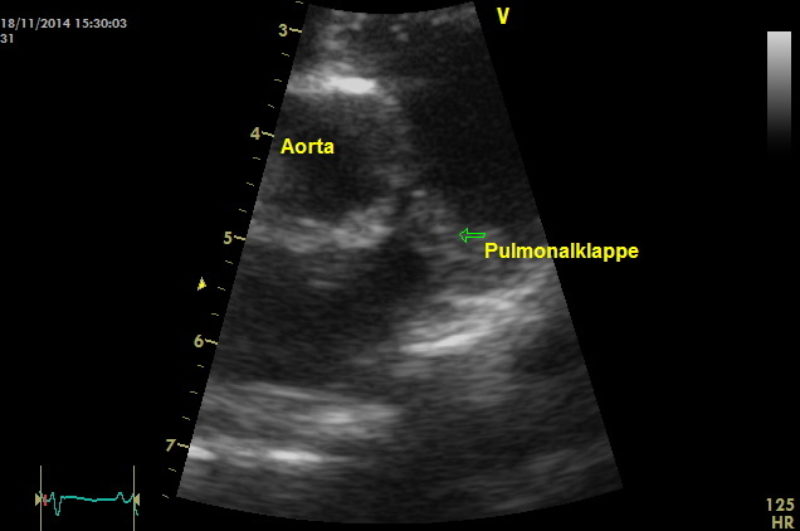

Im Herzultraschall zeigte sich eine hochgradig verdickte Muskulatur der Kammerwände der rechten Hauptkammer aufgrund einer hochgradigen Druckerhöhung. Es offenbarten sich außerdem angeborene Veränderungen der Mitralklappen und der Trikuspidalklappen. Bei der Darstellung der Pulmonalarterie zeigte sich eine missgebildete Pulmonalklappe, die wenig beweglich war. Zudem schloss und öffnete sie sich nicht vollständig. Die hochgradige Verwachsung der Pulmonalklappenöffnung führte zu einem sehr starken Anstieg des Blutdrucks von normalerweise 20 mmHg (Millimeter Quecksilbersäule) auf über 200 in der rechten Hauptkammer. Außerdem war der Klappenring der Pulmonalarterie sehr eng angelegt, wodurch der Schweregrad zusätzlich negativ beeinflusst wurde.